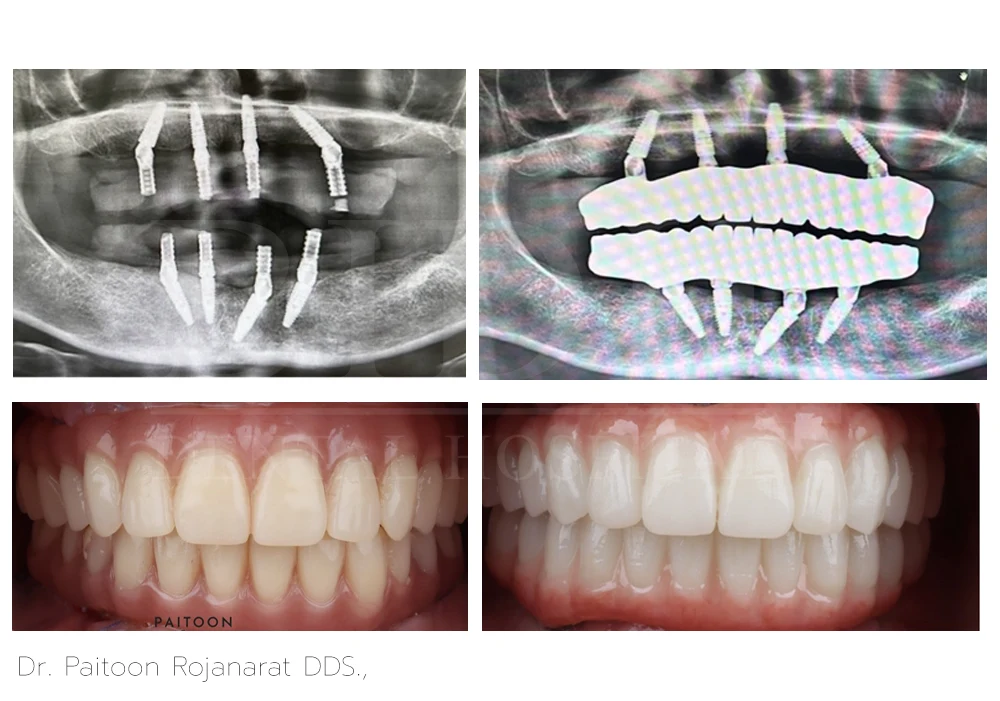

Dr. Paitoon Rojanarat DDS.,

Dr. Paitoon Rojanarat, DDS, is a dentist specializing on prosthodontics and esthetic dentistry that includes crowns, bridges, dental implants, veneers, and teeth whitening. With his highly-skilled and qualified expertise, he crafts custom-made fixed hybrid bridges over implants and dentures over implants designed for a natural appearance and a comfortable fit.